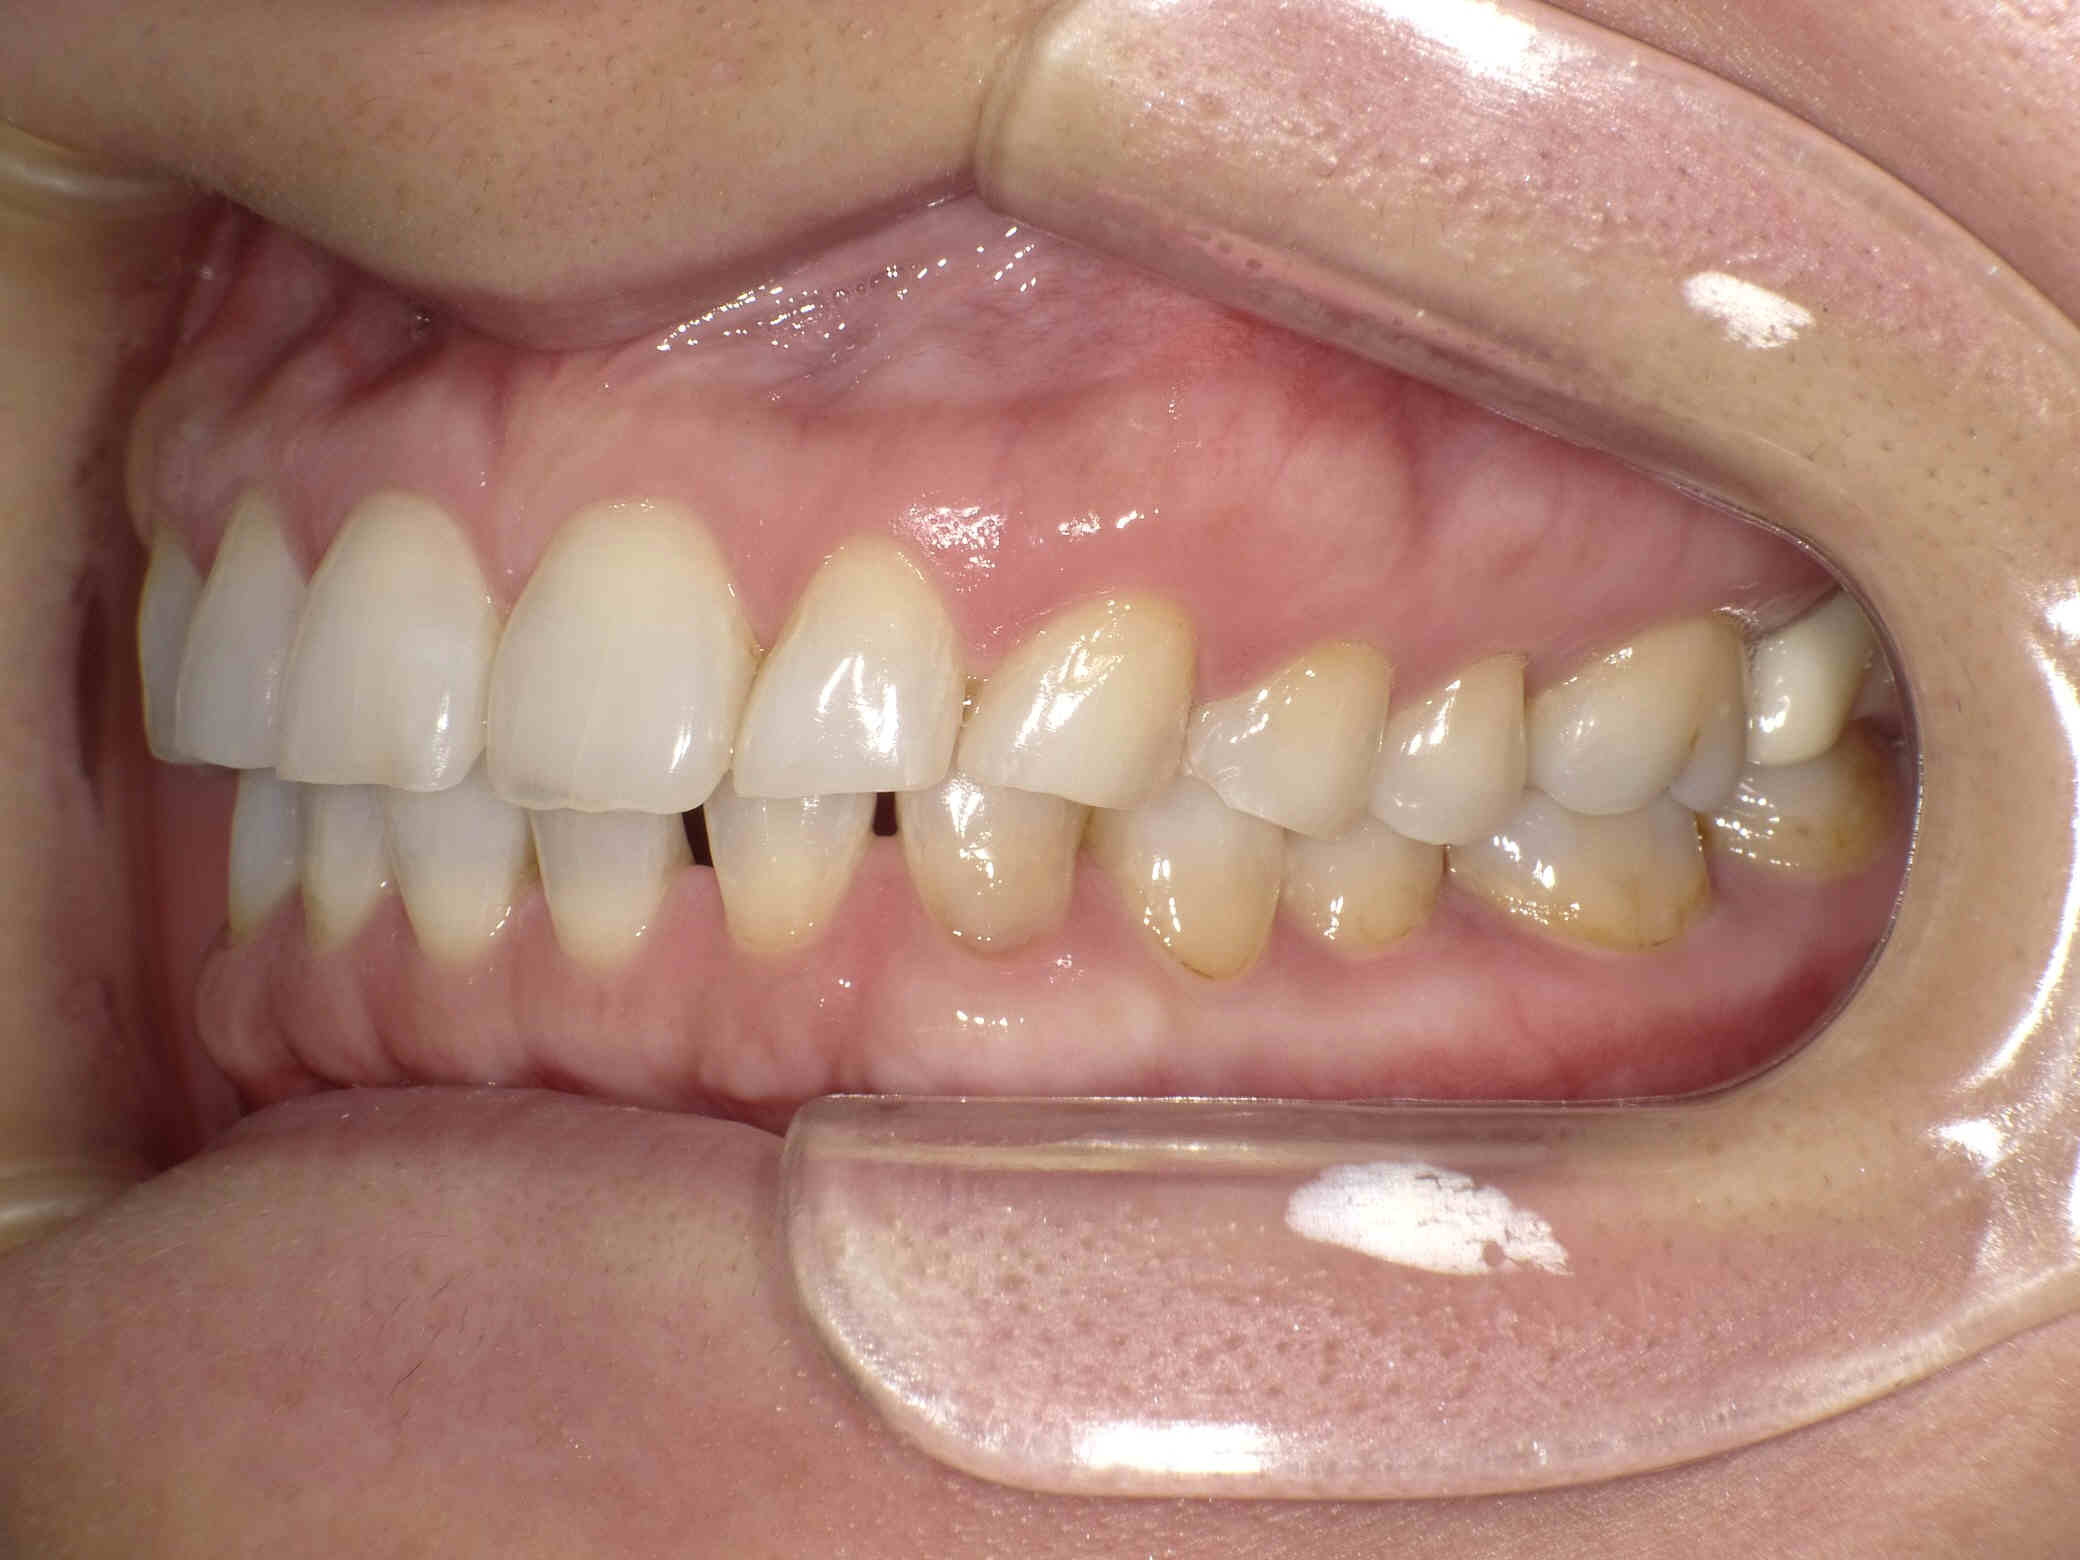

今回はご希望のマウスピース矯正で、食いしばりや歯ぎしりによる歯の破折やすり減りを予防しながら、歯と歯の隙間が広がって傾斜した前歯を元の位置に戻しました。

ホワイトニングも同時進行で施術し、白く輝く歯になりました。

元々入っていた臼歯のブリッジは治療せず、そのままの位置で矯正を行うことを希望されたため、正中(上顎と下顎の中心線)を合わせることは難しいですが、美しい歯列と口元へ仕上がりました!